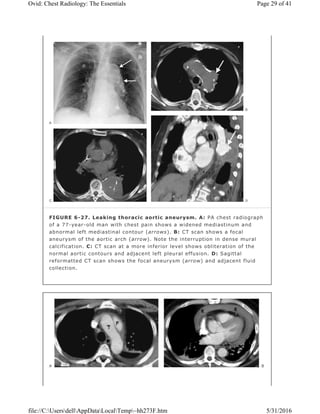

FIGURE 6-27. Leaking thoracic aortic aneurysm. A: PA chest radiograph

of a 77-year-old man with chest pain shows a widened mediastinum and

abnormal left mediastinal contour (arrows). B: CT scan shows a focal

aneurysm of the aortic arch (arrow). Note the interruption in dense mural

calcification. C: CT scan at a more inferior level shows obliteration of the

normal aortic contours and adjacent left pleural effusion. D: Sagittal

reformatted CT scan shows the focal aneurysm (arrow) and adjacent fluid

collection.